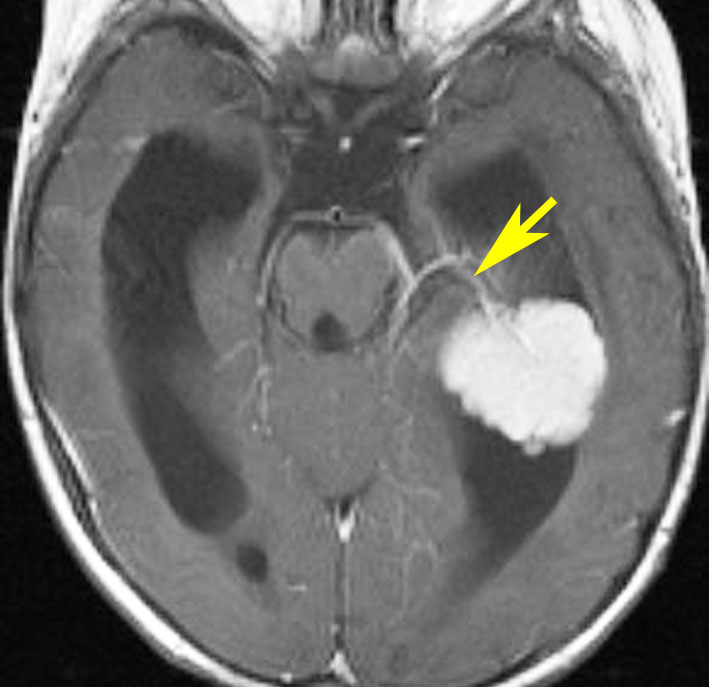

側脳室側頭角の脈絡叢乳頭腫です。黄色い矢印は腫瘍動脈で,前脈絡叢動脈といいます。ここを遮断すると出血が止められます。